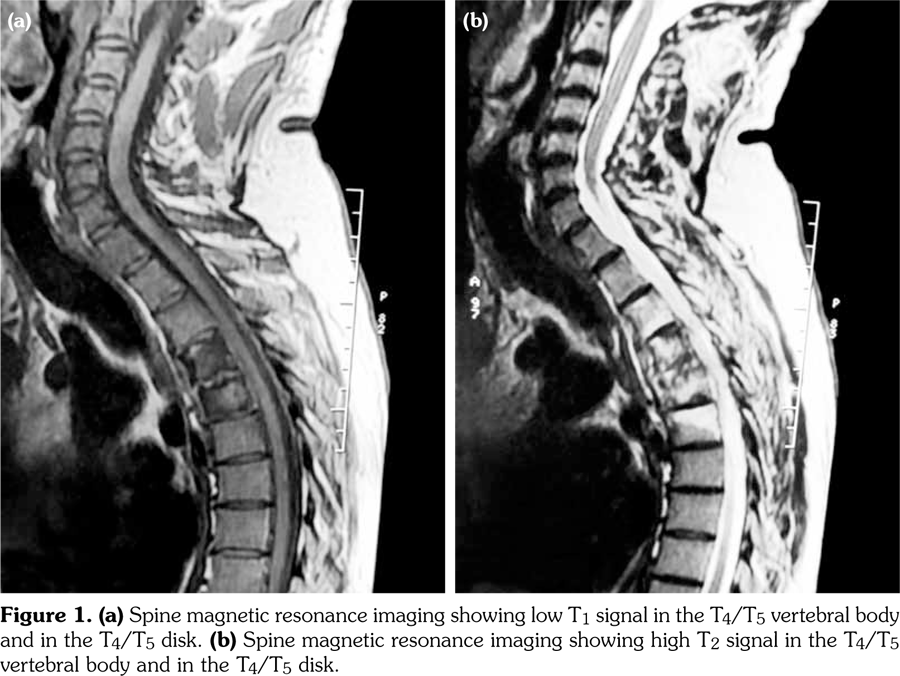

Thus, the diagnosis of SAPHO syndrome was established. Despite the use of nonsteroidal antiinflammatory drug, the disease remained active as attested by Bath Ankylosing Spondylitis Disease Activity Index at 6.7 at three-month follow-up. Then, the patient was lost to follow-up. One year later, he presented with hypesthesia and muscle weakness of his lower limb associated with kyphotic deformity and sphincter symptoms. He was unable to walk. Magnetic resonance imaging showed a vertebral collapse associated with spinal cord compression at T5 (Figure 3). Surgical treatment based on decompression and reconstruction with screw fixation was performed (Figure 4). The histopathology of the specimen obtained surgically showed nonspecific osteomyelitis with an infiltration of inflammatory cells and abnormal fibrous hypertrophy among the trabecular bone. One year later, etanercept was administered at a dose of 50mg weekly, leading to complete resolution of articular manifestations. Clinical remission was obtained under etanercept (Bath Ankylosing Spondylitis Disease Activity Index at 2.1). After two years of follow-up, patient’s paralysis improved by surgery, and he was progressively able to walk.